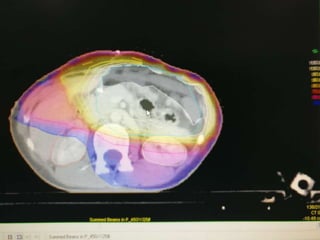

SIMULATION

 Supine

 Immobilization

 Arms : Overhead

 Legs : Knee support

 Oral and Intravenous contrast

Perez and brady’s principles and practice of radiation oncology (sixth edition)

Field Placement

Border Landmark Structures covered

Upper Bottom of T8/T9 Celiac axis, GE junction,

fundus, dome of

diaphragm

Lower L3 Gastroduodenal nodes

Left 2/3rd – 3/4th of left

hemidiaphragm

Fundus,

Supradiaphragmatic

nodes, Splenic nodes

Right 3-4 cm lateral to vertebral

bodies

Antrum, porta hepatis,

gastroduodenal nodes

PTV

 ITV : CTV + 1.5cm margin in all directions

 PTV : ITV + 5mm

Dose Constraints

 Spinal cord dose : 45 Gy

 Heart

 V30Gy < 30%

 Mean < 30Gy

 Liver

 V30Gy < 33%

 Mean < 25Gy

NCCN